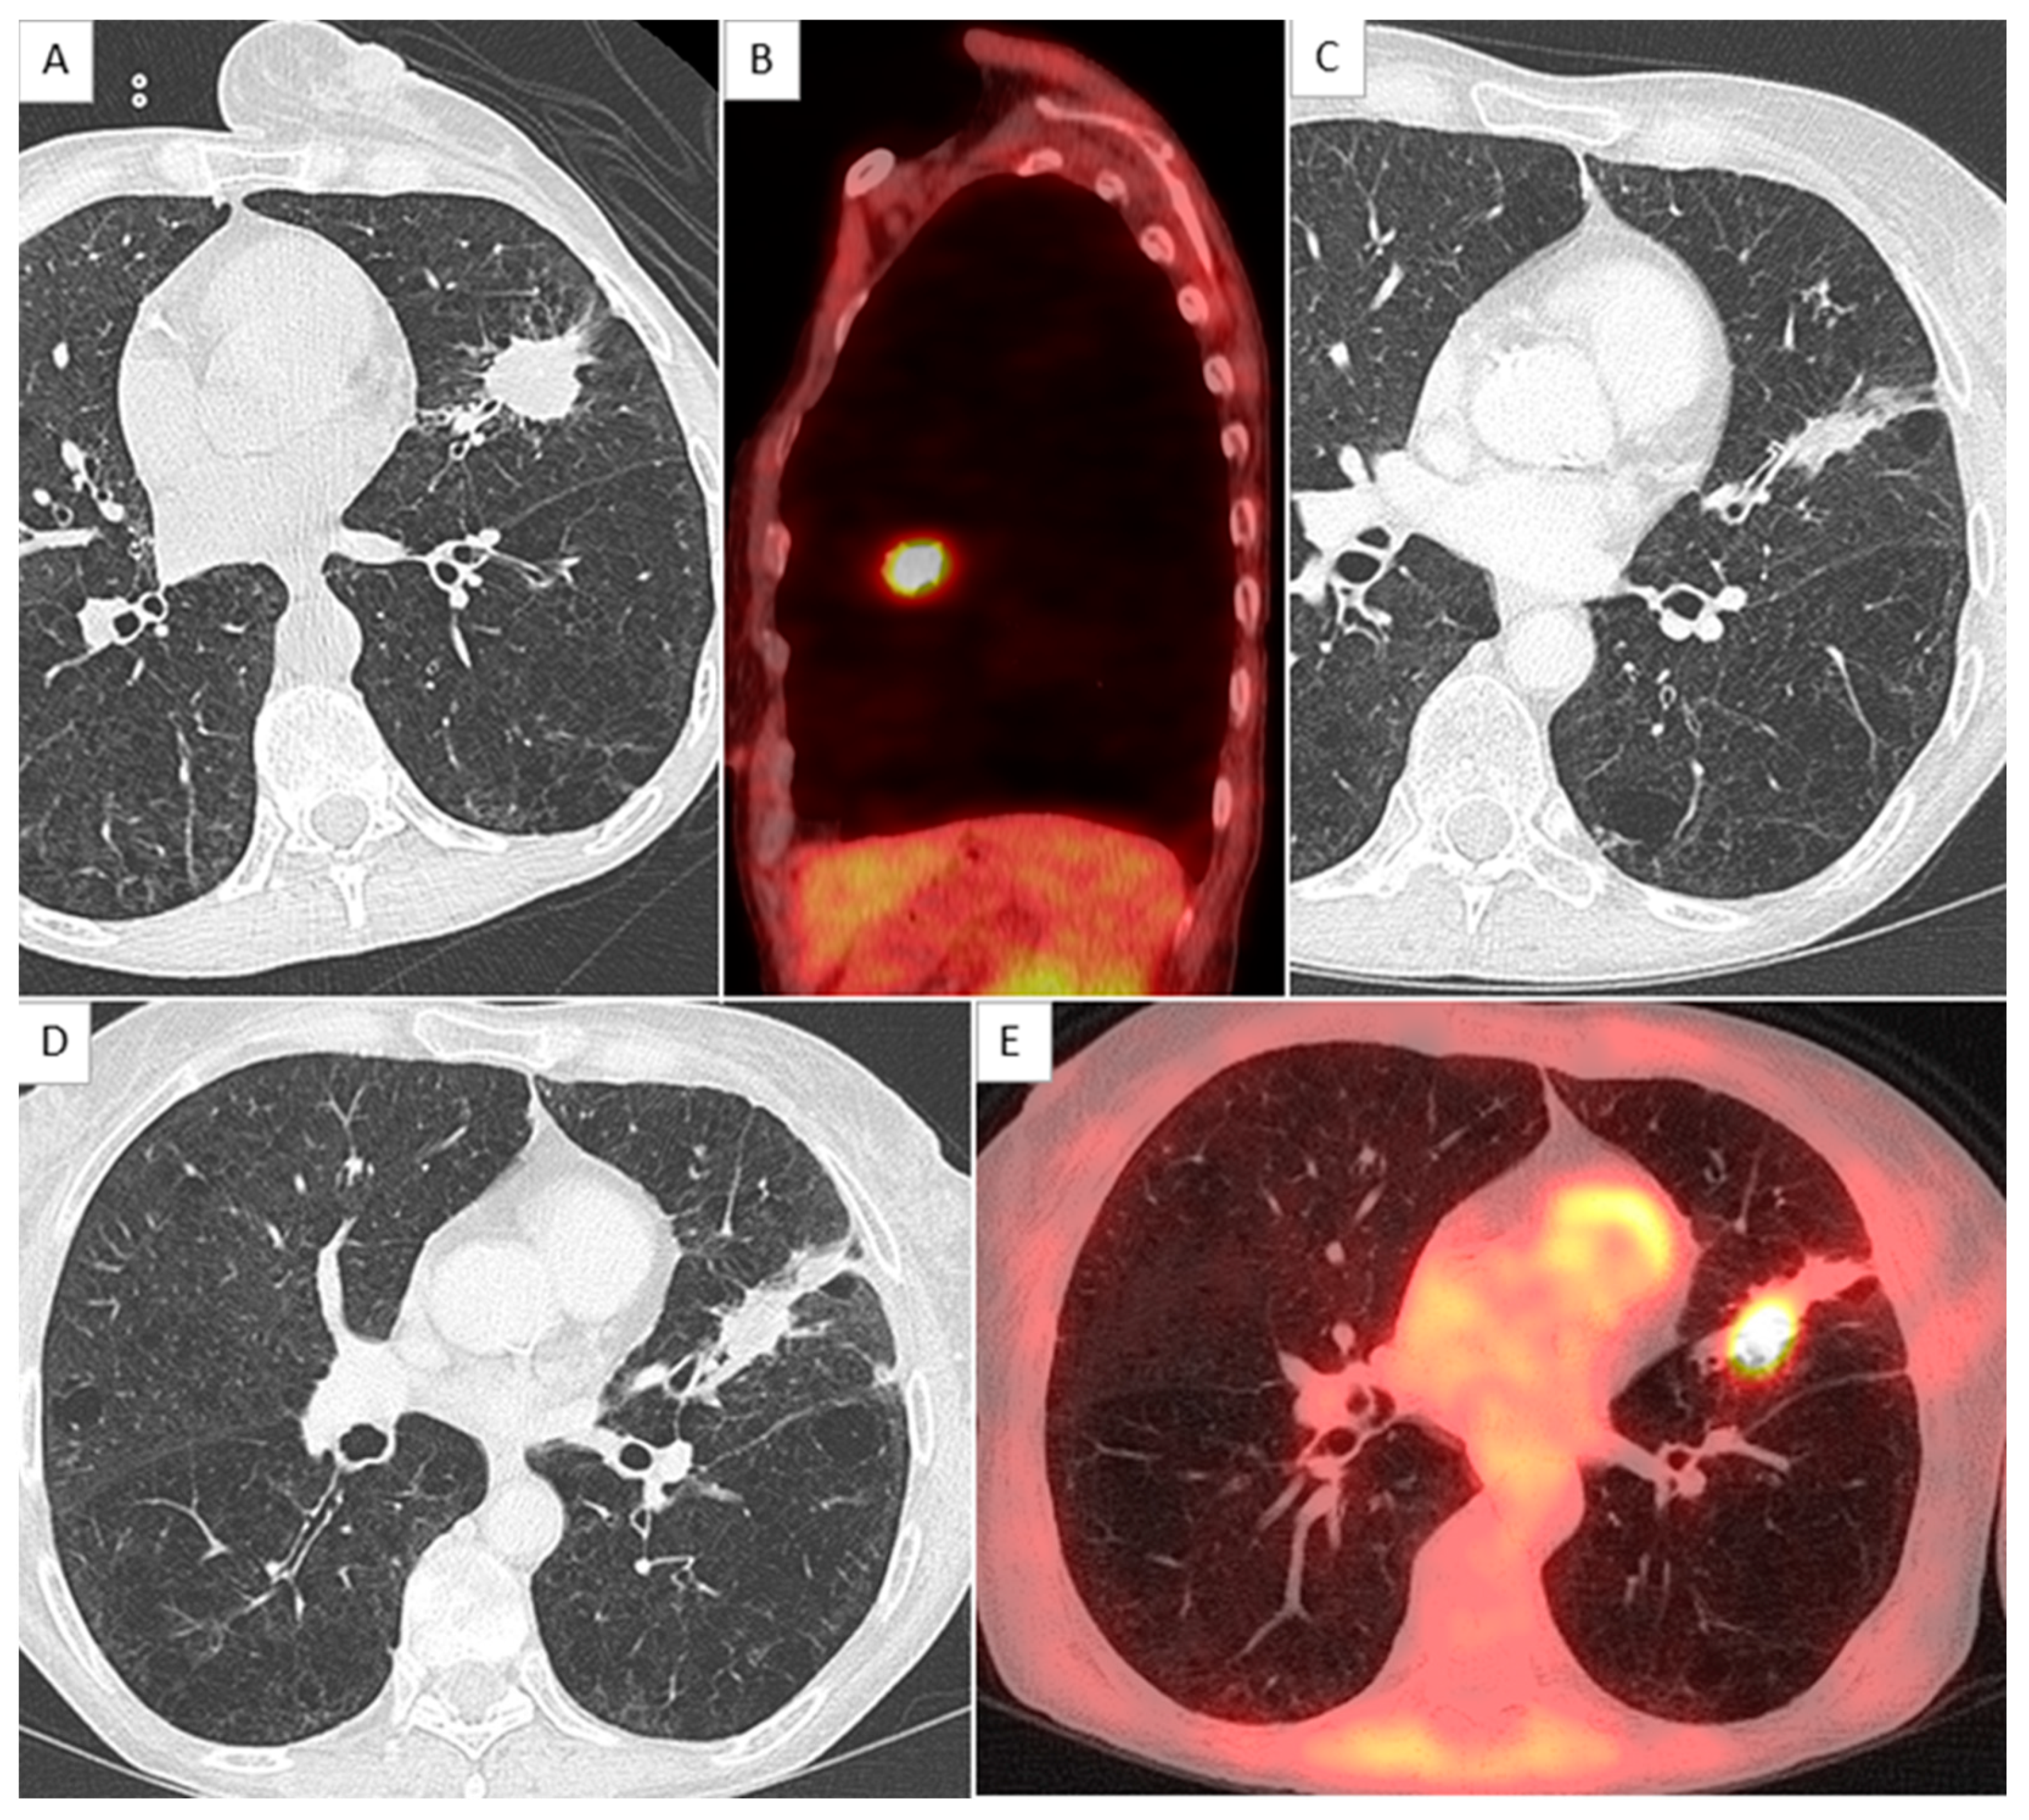

2.4. CT Scan Monitoring

2.5. Local Relapse Definition

- Kato, S.; Nambu, A.; Onishi, H.; Saito, A.; Kuriyama, K.; Komiyama, T.; Marino, K.; Araki, T. Computed tomography appearances of local recurrence after stereotactic body radiation therapy for stage I non-small-cell lung carcinoma. Jpn. J. Radiol. 2010, 28, 259–265. [Google Scholar] [CrossRef]

- Huang, K.; Dahele, M.; Senan, S.; Guckenberger, M.; Rodrigues, G.B.; Ward, A.; Boldt, R.G.; Palma, D.A. Radiographic changes after lung stereotactic ablative radiotherapy (SABR)—Can we distinguish recurrence from fibrosis? A systematic review of the literature. Radiother. Oncol. J. Eur. Soc. Ther. Radiol. Oncol. 2012, 102, 335–342. [Google Scholar] [CrossRef] [PubMed]

- Huang, K.; Senthi, S.; Palma, D.A.; Spoelstra, F.O.; Warner, A.; Slotman, B.J.; Senan, S. High-risk CT features for detection of local recurrence after stereotactic ablative radiotherapy for lung cancer. Radiother. Oncol. J. Eur. Soc. Ther. Radiol. Oncol. 2013, 109, 51–57. [Google Scholar] [CrossRef] [PubMed]